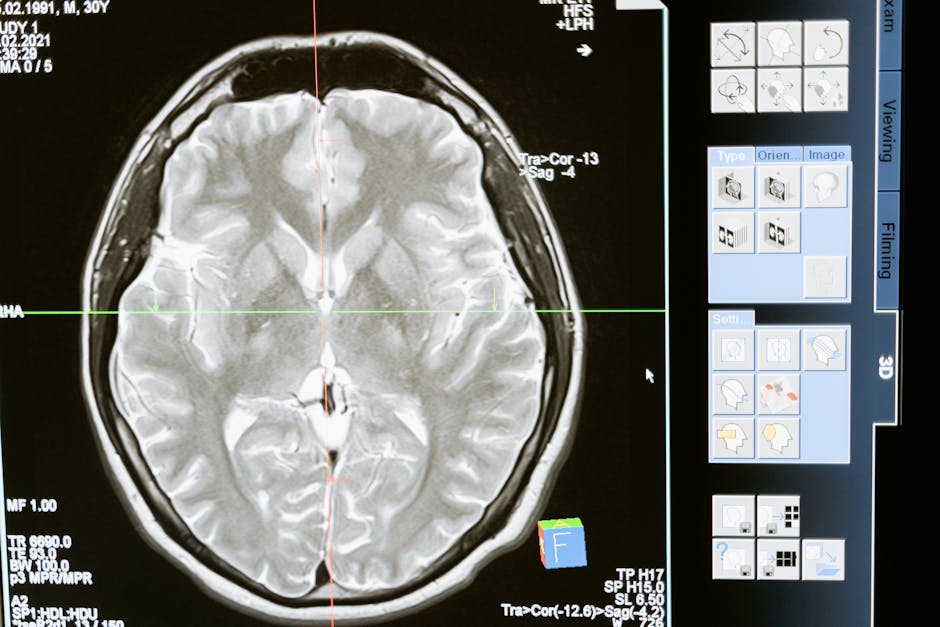

Brain mapping is a complex and time-consuming process that involves creating detailed maps of the brain’s neural connections. This process is crucial for understanding how the brain functions and how it is affected by various diseases and disorders. However, traditional brain mapping methods are often slow and labor-intensive, requiring scientists to manually analyze vast amounts of data. As a result, brain mapping research has been hindered by the lack of efficient and effective methods for analyzing and interpreting neural data. The development of AI-generated synthetic neurons has the potential to change this, enabling scientists to accelerate their research and gain new insights into the brain.

AI-generated synthetic neurons are computer-simulated neurons that mimic the behavior of real neurons in the brain. These synthetic neurons can be used to model complex neural systems and simulate the behavior of different brain regions. By using AI-generated synthetic neurons, scientists can test hypotheses and predict the behavior of neural systems, enabling them to gain a deeper understanding of the brain and its many complexities. The use of AI-generated synthetic neurons has the potential to revolutionize the field of brain mapping, enabling scientists to accelerate their research and make new discoveries.